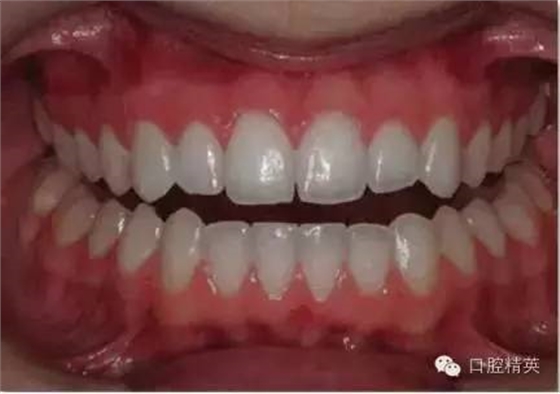

上下頜牙列照

正面觀

1:2 (1:3)放大倍率

需要使用拉鉤

• 上下頜牙應輕微張開使得切端清晰可見。這樣有利于切緣平面喝切緣楔狀隙的分析。

•露出盡量多的牙齦。對稱放置拉鉤,以免造成傾斜的假象。將拉鉤向遠離牙齒的方向拉。

•減少相片中嘴唇及拉鉤的影像。

•待治療的牙齒及周緣組織應能清晰可見。牙齦高度及輪廓應不被遮蓋。

•臉部中線應作為照片縱向中線。對其人中可能有些幫助,但是拉鉤有時會造成軟組織的偏斜。

•相片的水平中線為上牙切緣平面,垂直于縱向中線。

•相機應位于拍攝對象正前方,并與其成90°角。避免傾斜相機,或者發(fā)生垂直向角度偏斜的問題(俯拍或仰拍)。

•在中切牙及側切牙處對焦。選取適當的景深(通過高F值獲得)使得盡可能多的牙齒在焦距內。

•舌頭應往后縮,以免遮擋牙面。

•使用1:2 (1:3)放大倍率,使得上下頜牙弓均位于焦距內。